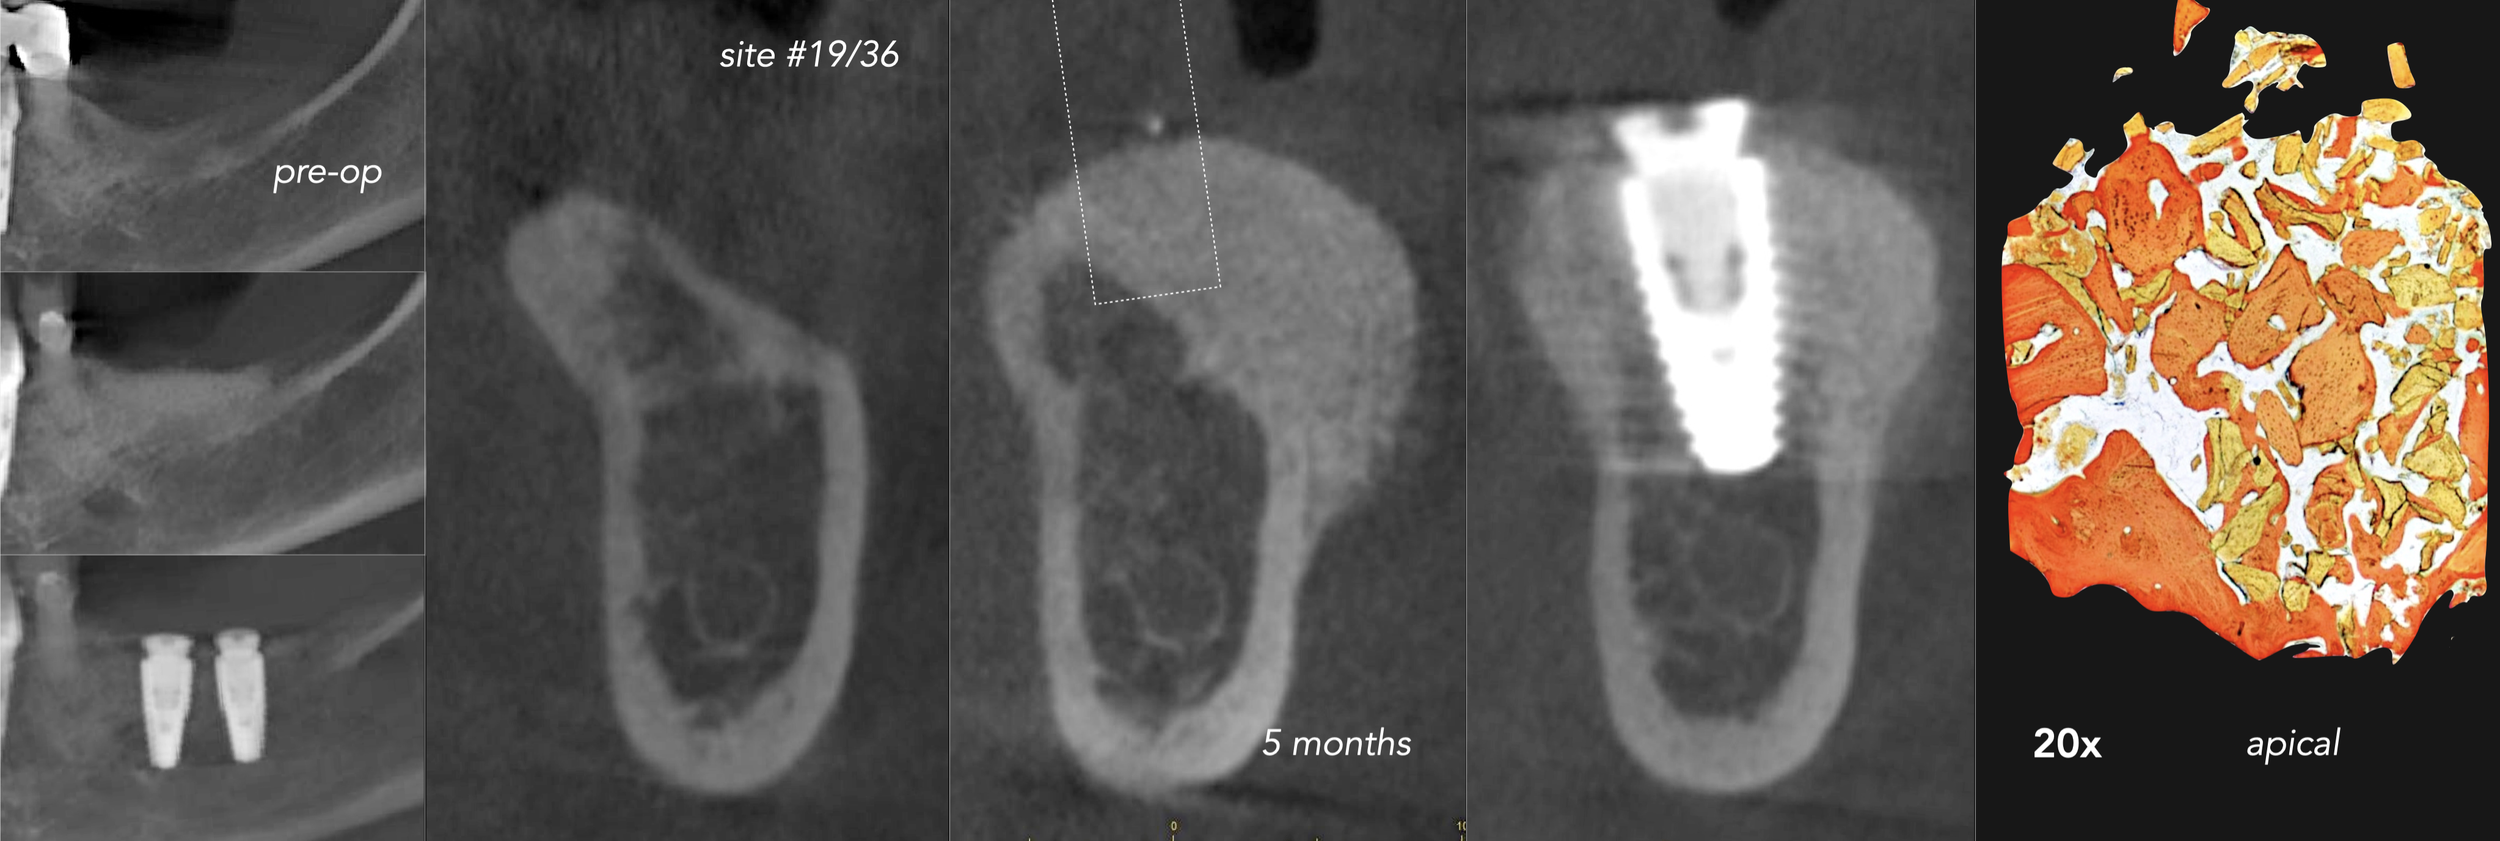

Clinical Cases CASE 1. COMPLEX IATROGENIC DEFECT CASE 2. CONGENITALLY MISSING LATERAL INCISORS CASE 3. VERTICAL AUGMENTATION CASE 4. VERTICAL AUGMENTATION CASE 5. IMPLANT BONE DEHISCENCE CASE 6. IMPLANT BONE DEHISCENCE CASE 7. KNIFE-EDGE RIDGE CASE 8. IMMEDIATE IMPLANT AND SIMULTANEOUS S.M.A.R.T.® HORIZONTAL AUGMENTATION CASE 9. IMMEDIATE IMPLANT AND SIMULTANEOUS S.M.A.R.T.® HORIZONTAL AUGMENTATION